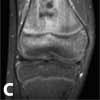

An MRI scan with gadolinium was ordered for further evaluation of the vague knee pain. It was performed using a 1.5-T magnet.

The MRI scan of the right knee revealed extensive marrow infiltration with multiple pockets of fluid in the distal femoral diaphysis and metaphysis measuring 7.4 3 1.5 3 1.5 cm. High signal was demonstrated on both T2-weighted fat-saturated and T1-weighted fat-saturated post-gadolinium sequences involving the medullary cavity and the surrounding cortex and periosteum (Figure 2). No subperiosteal fluid collection or fistulas were evident.

Figure C